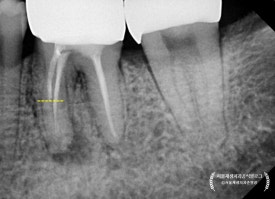

곧이어 치근단엑스레이를 찍어보았지요.

어금니는 뿌리가 여러개기 때문에, 경우에 따라 각도를 달리하여

2장 이상 촬영하기도 한답니다.

통상 아래 어금니에는 신경이 4개 (적으면 3개, 많으면 5개) 있게 마련이죠.

그런데 조금 이상합니다.

4개 중에 2개가 뿌리 전체 길이에 못미치게 치료가 되어 있습니다.

현미경을 이용해서

뿌리 끝까지 청소를 해 내려간 결과,

노랗고 빨간 고름이 뿌리 끝에서 퐁퐁퐁 솟아나는 것을 관찰할 수 있었습니다.

딱딱한 뼈 안에 고름이 차오르고 있었으니

얼마나 아팠을까요?

두번째와 뒤이은 세번째 내원날에는

모든 신경들을 뿌리 끝까지 청소하기 위해 노력했습니다.

나중에라도 통증을 일으킬 수 있는 원인을

준원장의 정성에 하늘이 감동하셨는지,

아래 어금니의 모든 신경을 깨끗하게 청소하는데 성공하였고,

고름도 더 이상 나오지 않았습니다!

세 번의 내원만에 얻어진 값진 결과입니다.

치아 내부에 소독 약제를 뿌리 끝까지 도포하였습니다.